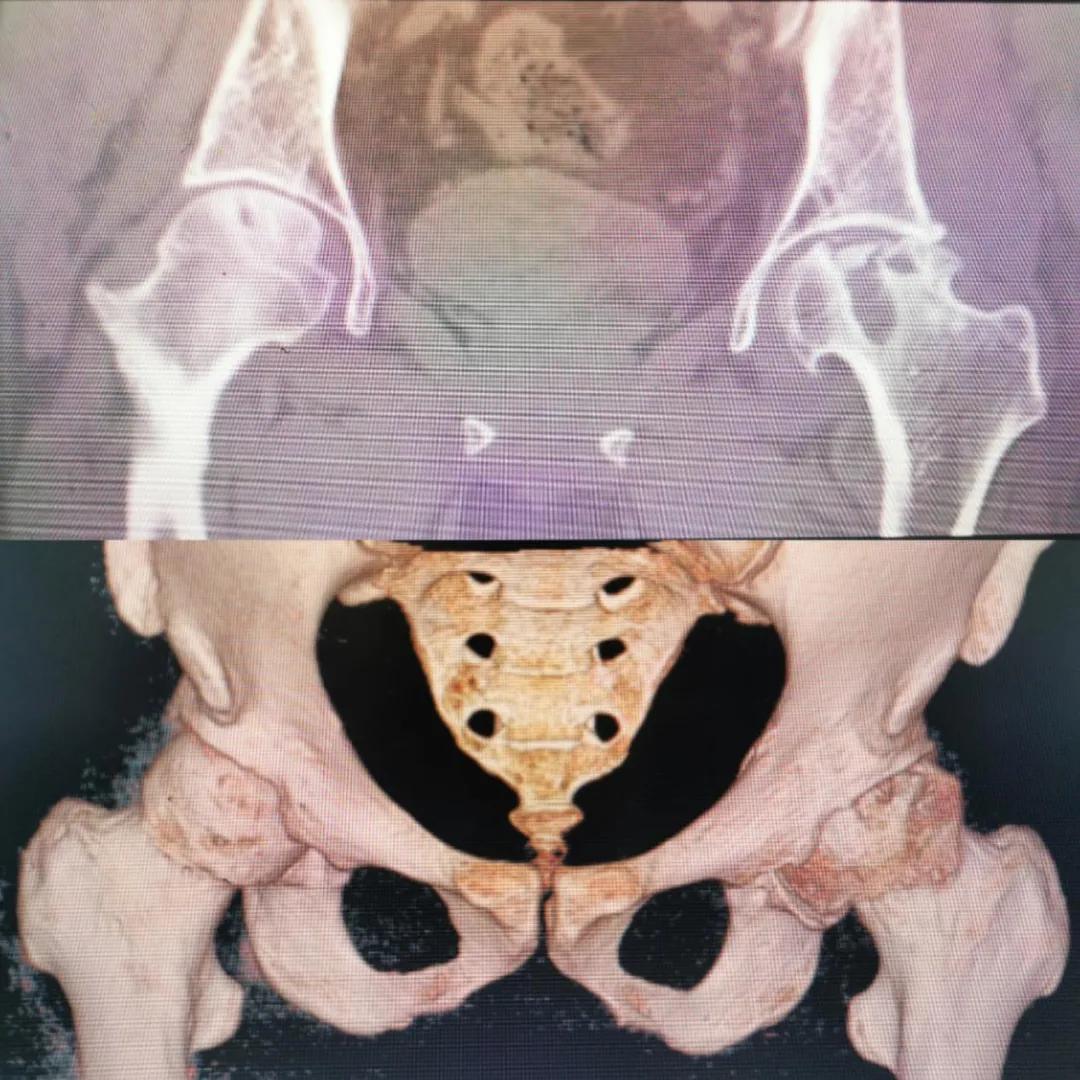

入院急查血結果提示炎癥反應,感染較重,凝血功能及肝功均不同程度損害;髖關節(jié)磁共振(MRI)檢查提示雙側股骨頭缺血壞死,繼發(fā)髖關節(jié)炎,左側髖周軟組織腫脹。醫(yī)療團隊給出的初步診斷為膿毒血癥、股骨頭缺血性壞死、軟組織感染、皮膚潰瘍及閉孔神經損傷。

圖片(圖為患者入院時髖部CT檢查)

追溯病史,患者訴前不久曾用蜂蜇療法治療股骨頭壞死,每日4次,每次100只蜜蜂蜇雙臀部、髖部,這才導致了病情急劇進展。查明了來龍去脈,我院智能微創(chuàng)骨科醫(yī)護團隊與患者家屬積極溝通病情,給予特殊級抗生素抗感染以及消腫、止痛等支持治療,同時對潰瘍創(chuàng)面進行專業(yè)、規(guī)范的清創(chuàng)、換藥處理,保護創(chuàng)面降低感染程度;護理上輔助翻身,減少壓力性損傷。